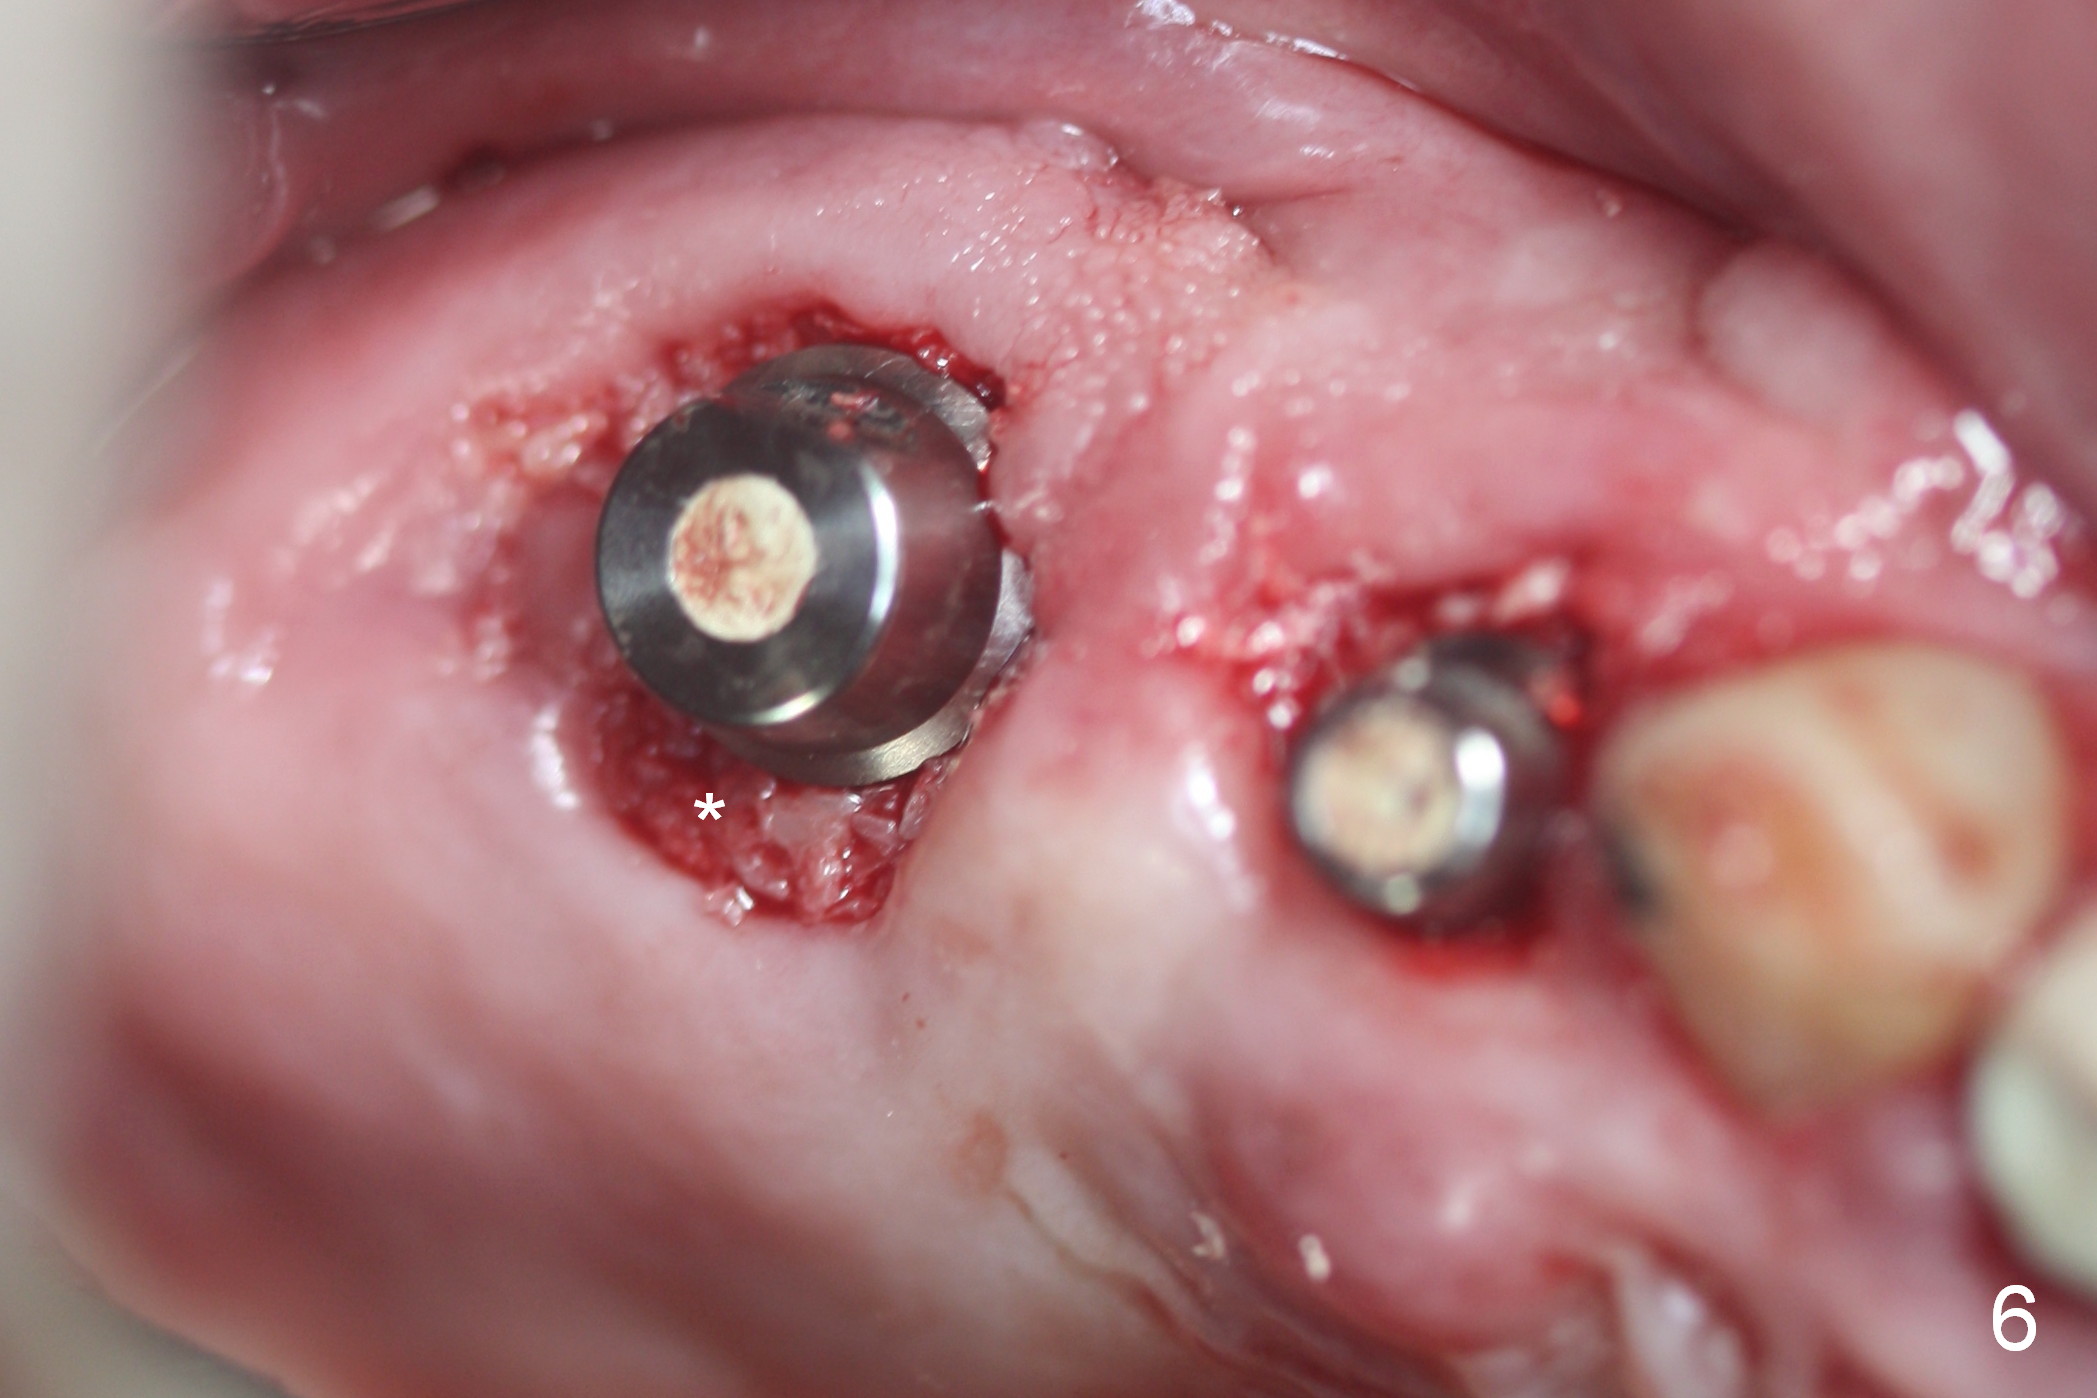

Preop photos show generalized gingival hyperplasia (hypertension med (Amlodipine, Calcium Channel Blocker), Fig.1 *), palatal (Fig.2<) and buccal (Fig.3 B) abscesses originated from the tooth #5. There is a smaller abscess buccal to the tooth #3 (not shown). After extraction, the buccal and palatal plates of the teeth #3 and 5 are found basically non-existent. When taps are placed, large socket defects are evident (Fig.4 *). In addition to sinus lift at #3 (Fig.5 black *), mineralized cancellous and cortical allograft (.5-1 and 1-2 mm) is placed around the implants with healing screws in place (white *). After the healing screws are removed and cemented abutments are placed, more allograft is packed (Fig.6-8 *). Closing the "dead" space in step may prevent immediately postop infection and peri-implantitis.